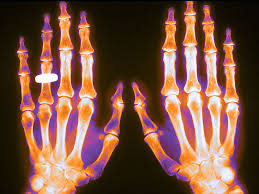

Osteoporosis y Evaluación del Riesgo de Fracturas y toma de decisiones compartidas en la Práctica Clínica

JAMA, 17 de enero de 2017 Las fracturas debidas a la osteoporosis representan un serio y costoso problema de salud pública, que conduce a la discapacidad y a un mayor riesgo de mortalidad. Para las mujeres posmenopáusicas, las fracturas osteoporóticas son más comunes que el ictus, el infarto de miocardio y el cáncer de mama combinados.